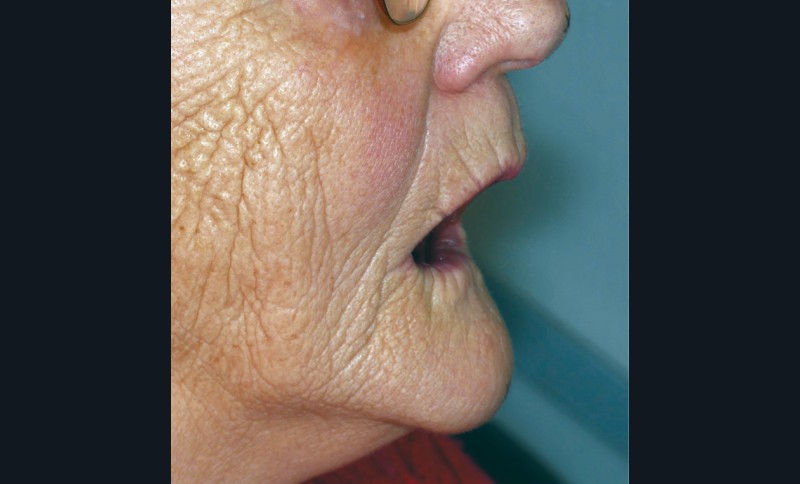

La sous-évaluation, quant à elle, engendre un impact esthétique avec un affaissement de l’étage inférieur de la face. Le patient paraît vieilli, avec un approfondissement des rides et sillons du visage, le menton avance (fig. 2). La déglutition peut être inconfortable, avec une interposition labiale fréquente. Toutefois une légère sous-évaluation engendre peu de conséquences ; le patient aura même tendance à se sentir plus confortable avec ses prothèses.